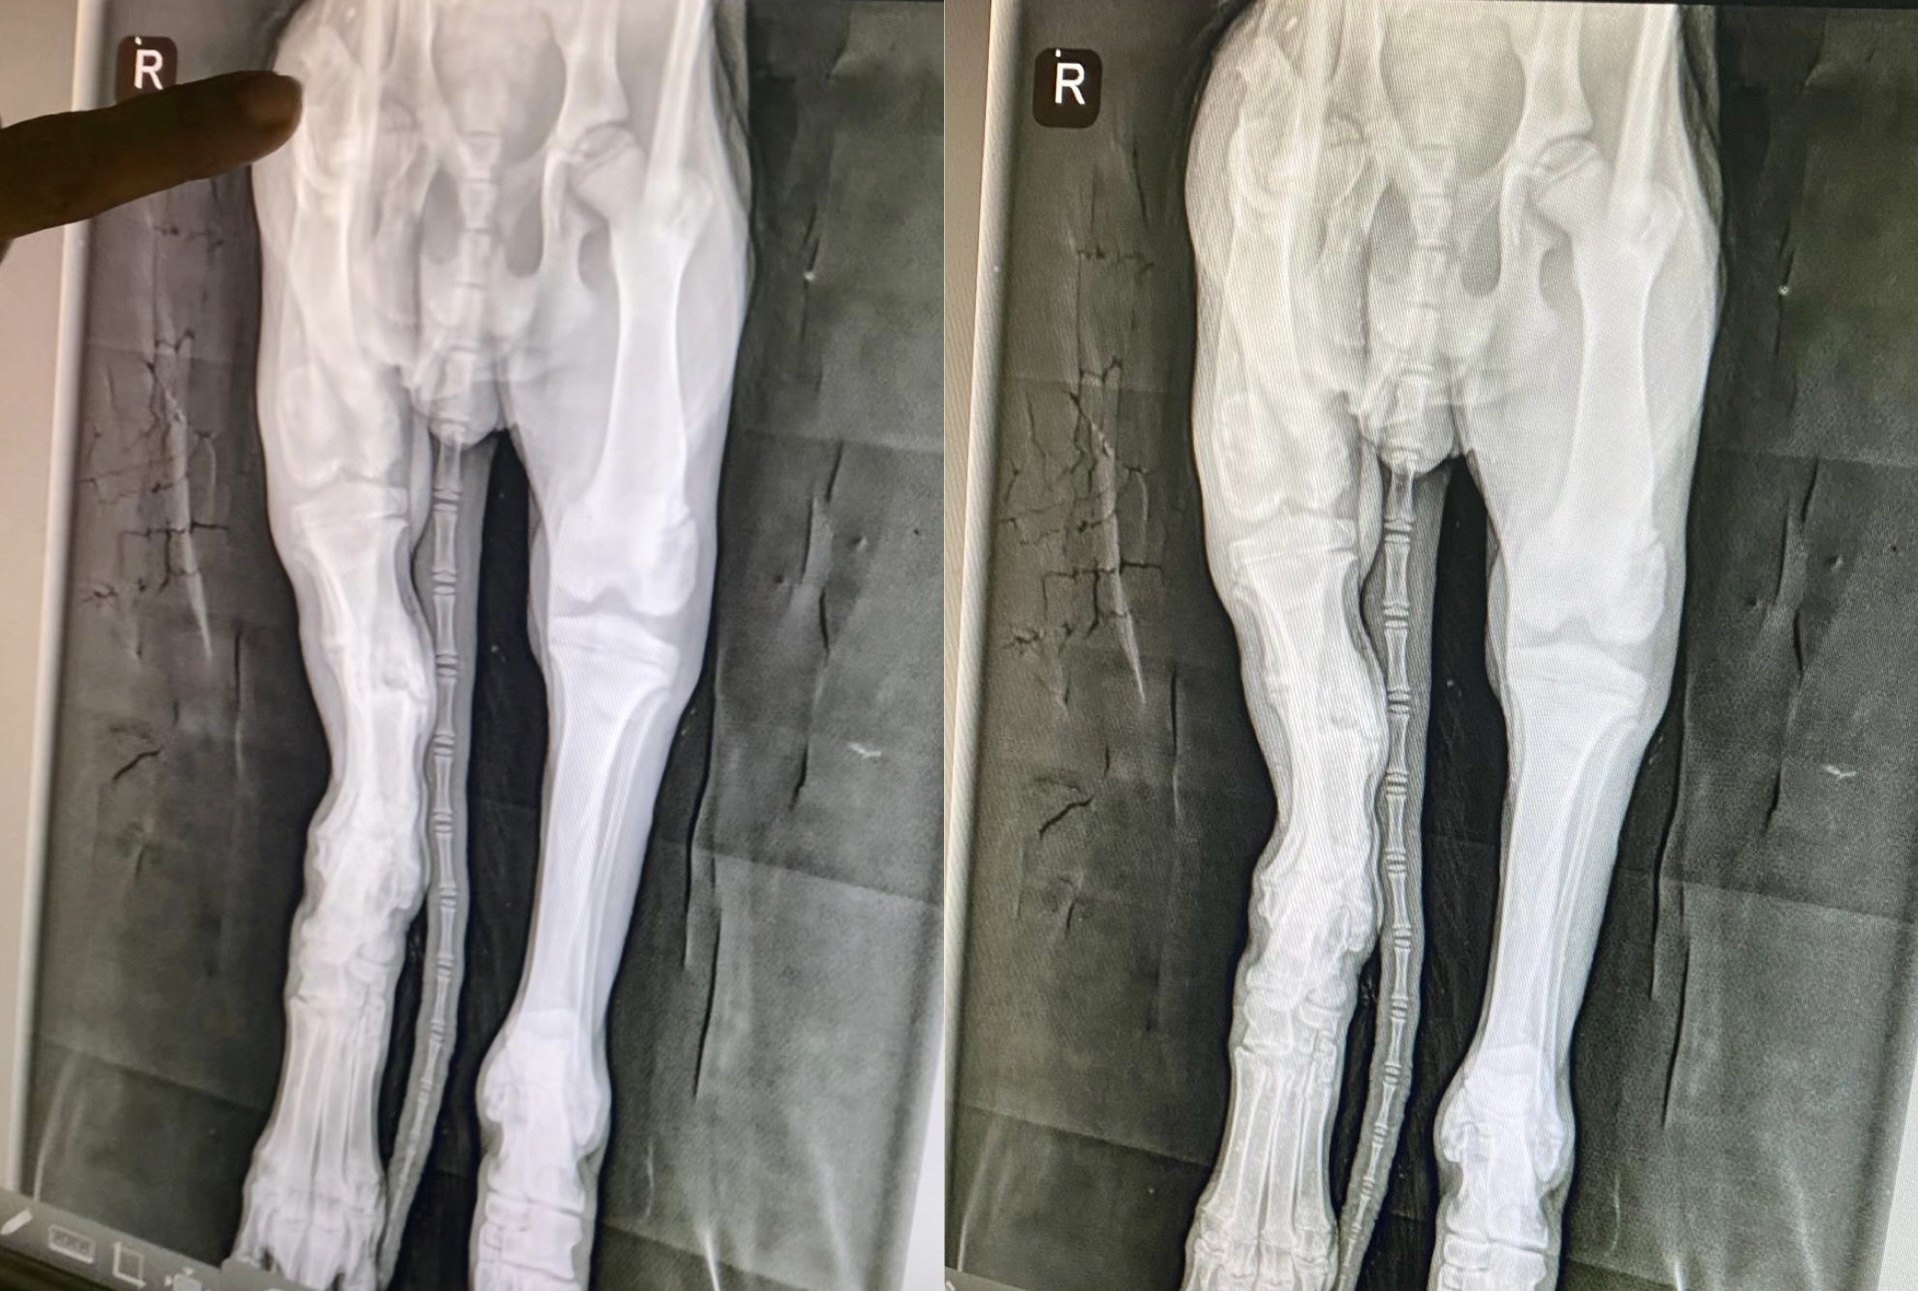

In October, while wandering the streets of Palmdale, CA, this 10-week-old stray puppy, who we named “Angel,” suffered alone on the roadside after being hit by a car, already frail from malnourishment, now facing a new, excruciating agony—a fractured leg from the accident.

Angel suffered multiple fractures and will soon be reassessed to determine if she’s ready for surgery. Her road to recovery has been costly, but every donation makes a significant difference.